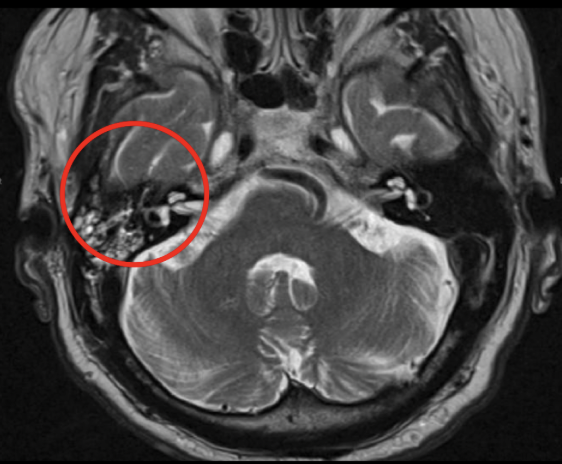

Q

Diagnóstico probable

A

Otitis media

La RM está indicada en las complicaciones de la otitis media, ¿Coque veras en la secuencia T1 y T2?

T1: masa hipointensa en oído medio

T2: masa híper intensa en oído y mastoides